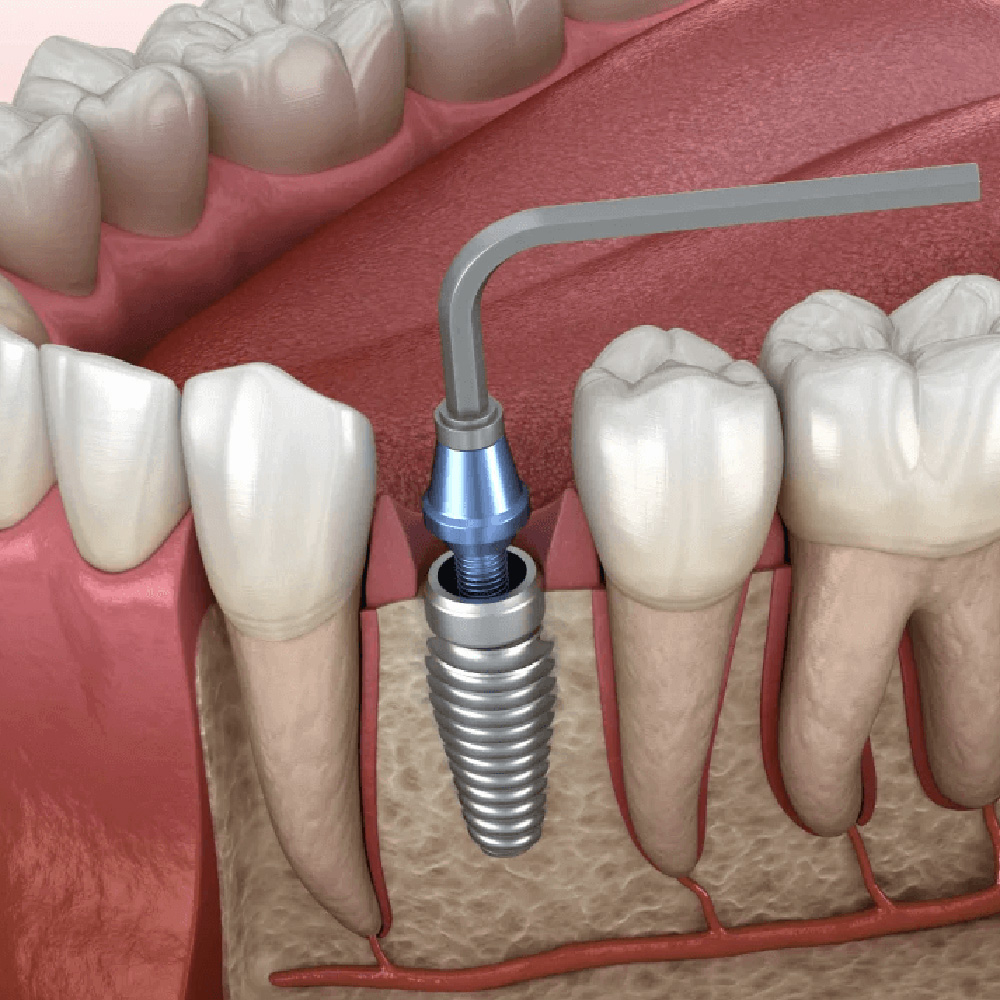

ایمپلنت فوری چیست؟

ایمپلنت فوری روشی پیشرفته در دندانپزشکی است که در آن پایه ایمپلنت (پیچ تیتانیومی) و روکش موقت در یک جلسه یا در مدت زمانی بسیار کوتاه قرار داده میشود. این روش برای بیمارانی که به دنبال نتایج سریع و باکیفیت هستند، ایدهآل است.

- مشاوره و ارزیابی اولیه: بررسی دقیق وضعیت دهان و دندان با استفاده از تصویربرداری پیشرفته (مانند CBCT) برای اطمینان از مناسب بودن شرایط برای ایمپلنت فوری.

- طراحی دیجیتال: برنامهریزی دقیق محل کاشت ایمپلنت با استفاده از نرمافزارهای پیشرفته برای دستیابی به بهترین نتیجه.

- کاشت ایمپلنت و نصب روکش موقت: قرارگیری پایه ایمپلنت و روکش موقت در یک جلسه، با دقت و مهارت توسط تیم متخصص.

- نصب روکش دائم: پس از دوره بهبودی (معمولاً چند ماه)، روکش دائم با طراحی سفارشی جایگزین روکش موقت میشود.